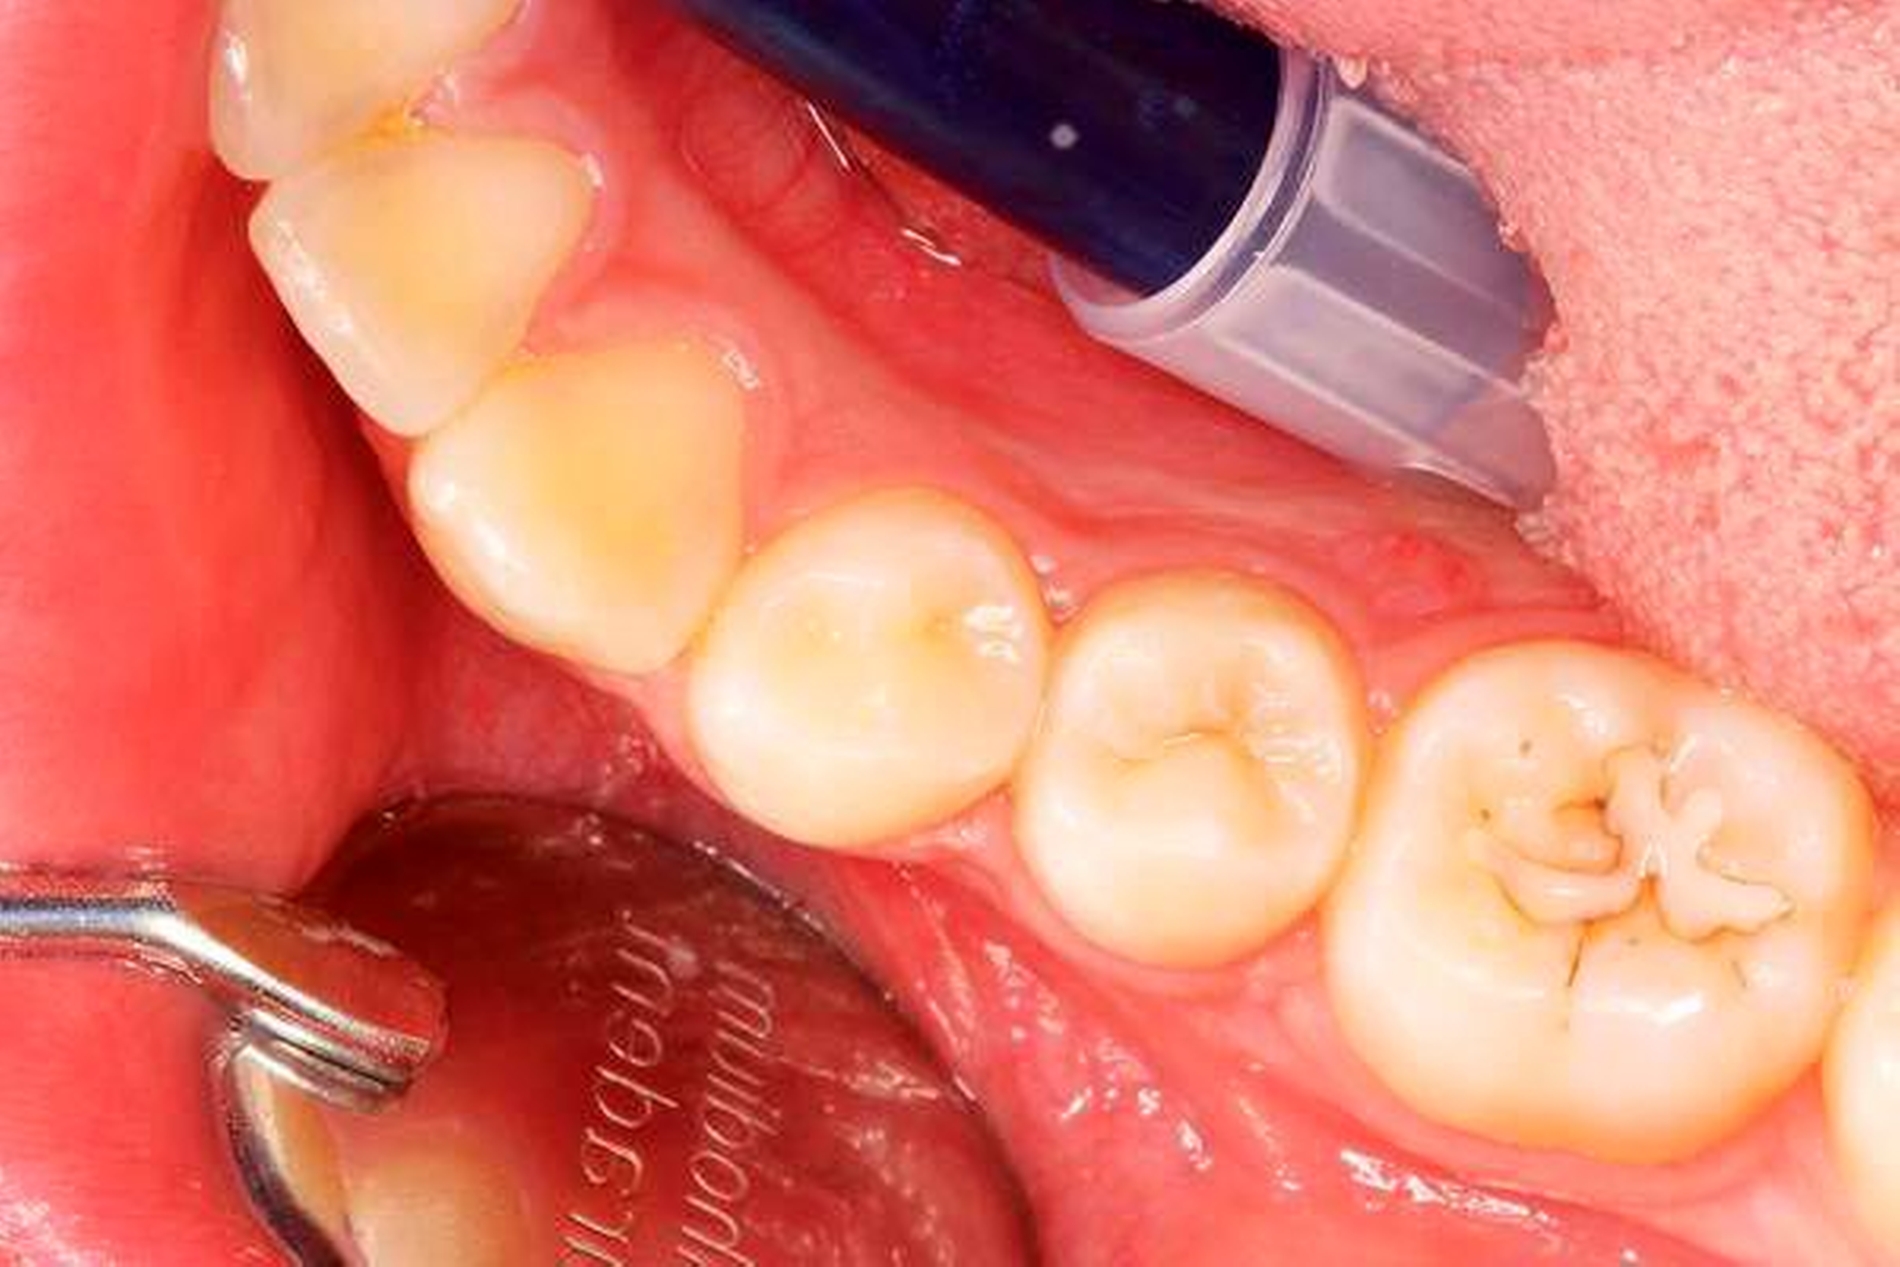

Klinisch stellte sich der Zahn als nicht perkussionsempfindlich dar und reagierte nicht auf den Kältetest. Es lag keine Schwellung vor, jedoch ein Fistelgang lingual des Zahnes 45 (Abbildung 2) sowie eine leichte Druckdolenz im Vestibulum Regio 45. Eine große Kavitation, wie es das Röntgenbild vermuten lässt, war klinisch nicht festzustellen (Abbildung 2). Die Nachbarzähne reagierten adäquat auf den Kältereiz und waren perkussionsunempfindlich. Die Fissurenversiegelung an Zahn 46 wurde als insuffizient bewertet.